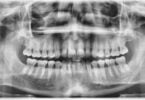

Análise de radiografias dentárias com base em IA poupa...